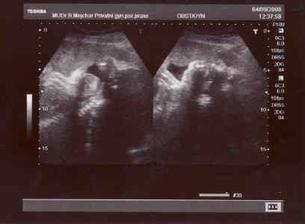

4.9. - na kontrole byl s námi i tatínek a beruška na nás pěkně plazila jazyk 🙂)...jsme pěkný obříci, vážíme už 2,7 kg :-O¨